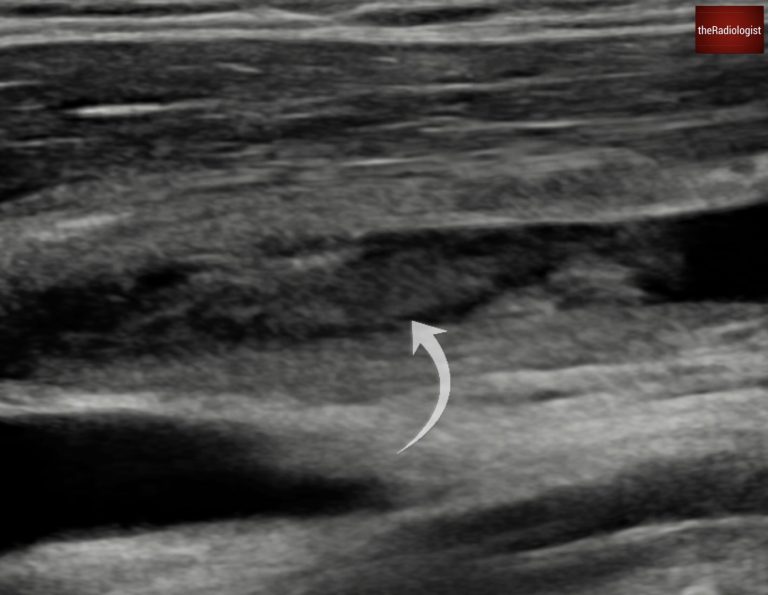

In this case, the patient reported a sore throat one week prior to becoming acutely ill. An ultrasound of the internal jugular vein was performed, revealing a large clot, confirming Lemierre Syndrome.

There is thrombus within the internal jugular vein.